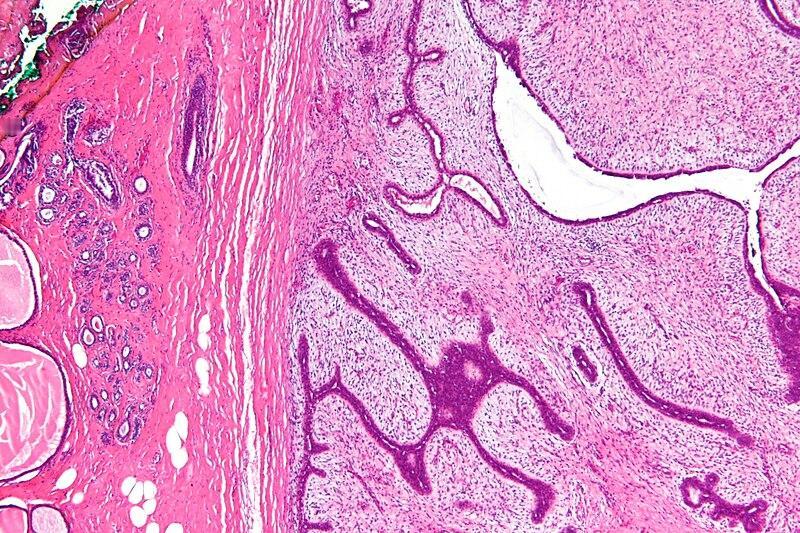

24岁的杭州女孩小刘, 为了拼事业经常熬夜,一年后洗澡时突然发现右乳里长了个拳头大的硬疙瘩,她还以为是正常的经期胀痛,没当回事。可谁知道,这疙瘩长得飞快,一年后直接长到了12厘米,几乎把整个右乳都撑得满满的! 去医院检查后,医生告诉她这是“叶状肿瘤”——虽然大多是良性的,但长得特别快,要是再拖下去可能就危险了。手术的时候,医生特意选了隐蔽的切口,还放了假体,这样乳房的形状能保持好看。手术后小刘才后怕:“早知道这样,当初就该早点来医院的...” 医生特别提醒:发现乳腺上有肿块,千万别拖着不管!叶状肿瘤就跟野草似的,要是不早点彻底处理掉,很可能会反复长。特别是年轻的女孩子,工作再忙,每个月洗澡的时候,花一分钟自己检查一下,就能避免大问题找上门。 有网友就说:现在的年轻人啊,真是太拼了!体检报告都不敢看,小毛病拖成了大问题,最后还得躺手术台。你身边有没有这样“硬扛着不吭声”的职场人呢?你平时会给自己做乳房自检吗?评论区聊聊你的小习惯吧~